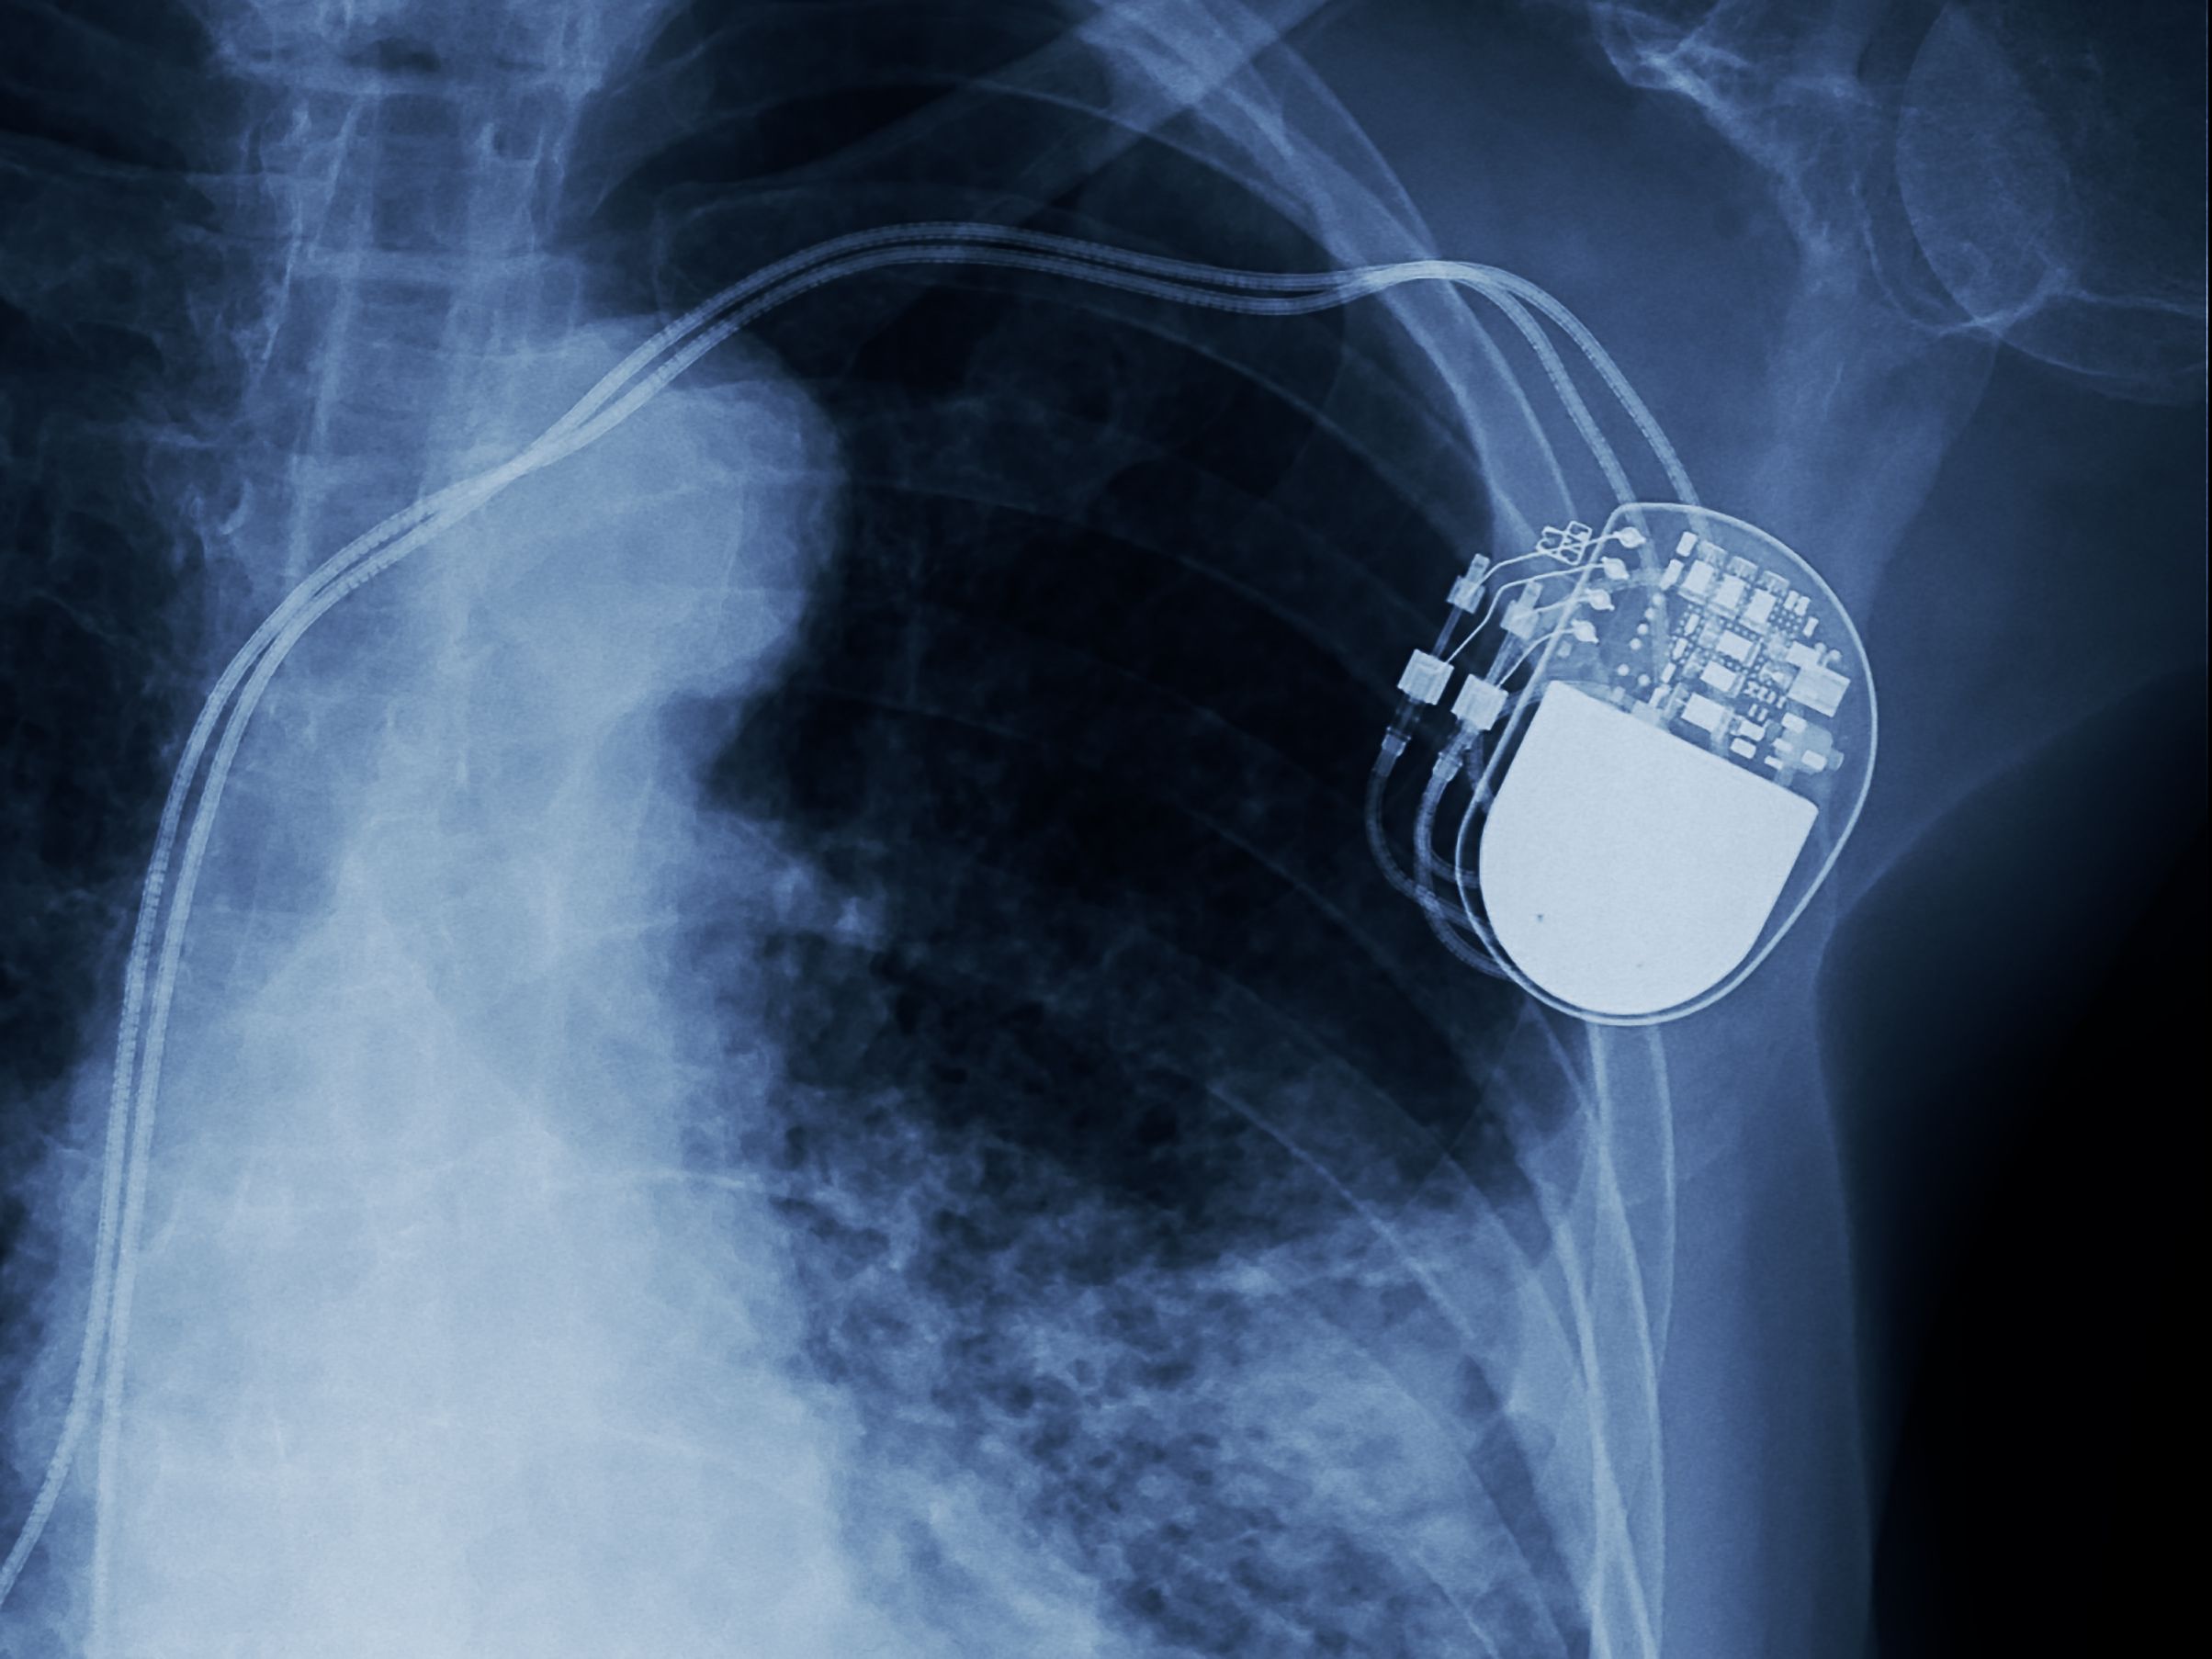

A spinal cord stimulator (SCS) is a device, similar to a pacemaker, that is surgically implanted under the skin. It delivers low levels of electrical pulses directly to the spinal cord to block pain signals before they reach the brain. Mechanically, the leads that deliver the electrical pulses can move or break, requiring revision surgery. Additionally, the battery may wear out. But there are there are more than mechanical complications.